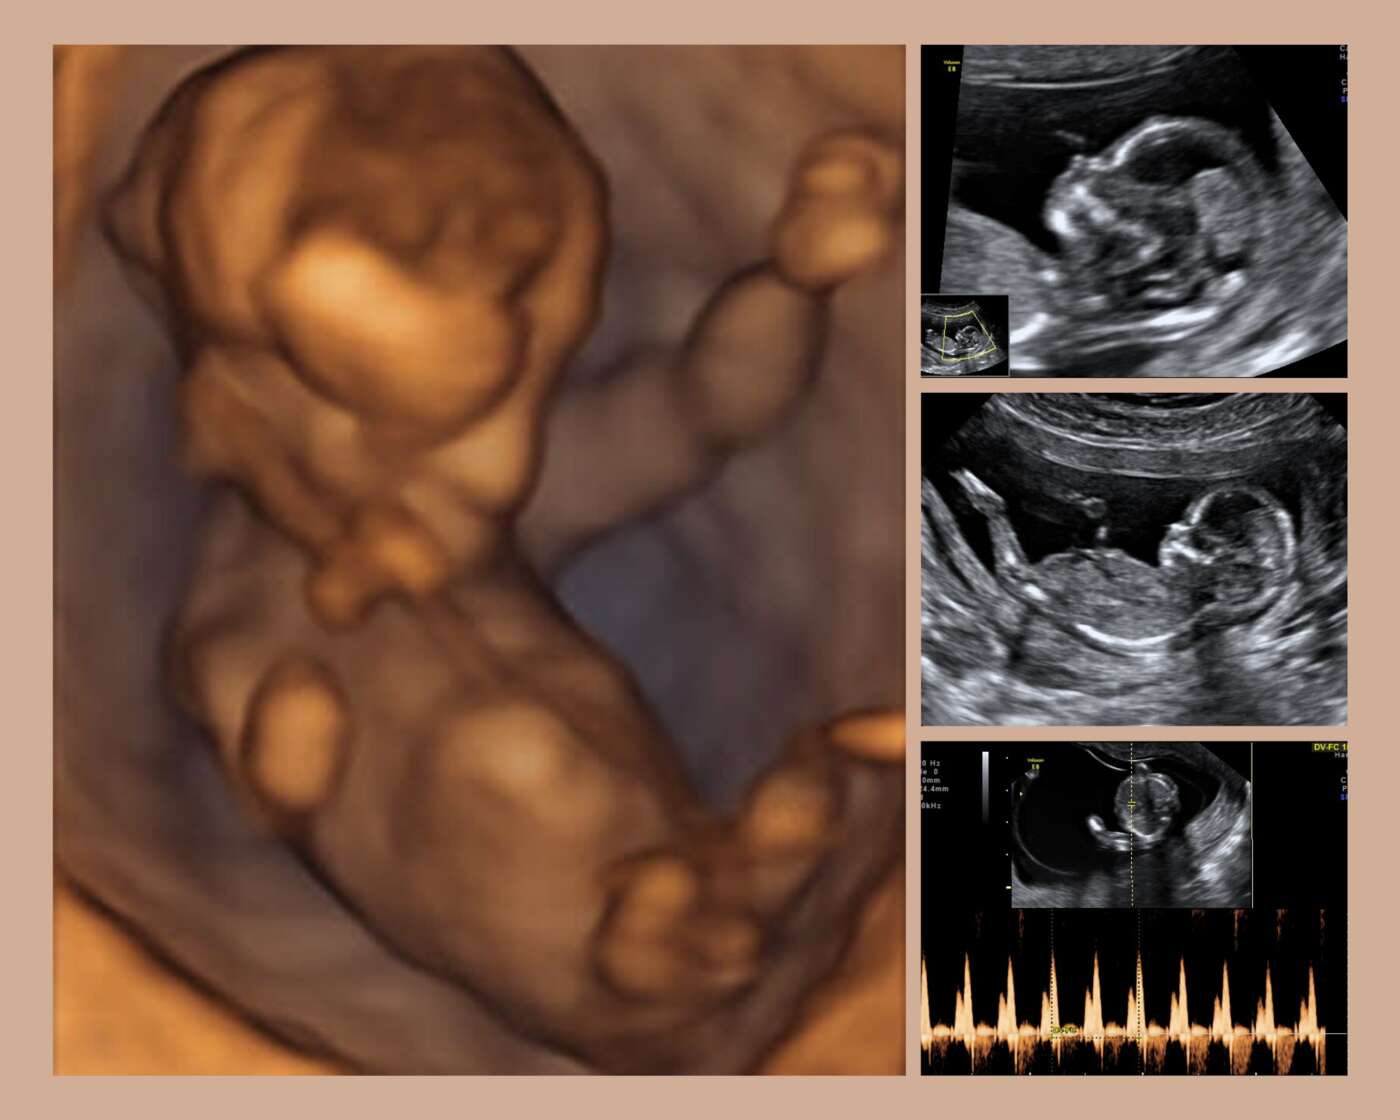

Qu es el tamizaje prenatal y cu ntos tipos existen bbmundo store, Tamizaje maternal una prueba de control para embarazadas CSS store, Momprenatal Fetal Medicine Center Conoces nuestro examen de store, Tamizaje como cuidado prenatal La Prensa Panam store, Tamizaje Fetal qu es s ntomas y tratamiento Top Doctors store, Tamizaje del primer trimestre con ultrasonido Sonograma gen tico s store, Tamizaje Prenatal Dianne Galicia uDocz store, TAMIZAJE UNA PRUEBA PARA DESCATAR ANOMAL AS EN EL FETO store, Lab Center TAMIZAJE Expertos en pruebas del embarazo store, Esto es todo lo que tienes que saber sobre la prueba de tamizaje store, Prueba de tamizaje predice riesgo de complicaciones en el embarazo store, Ecograf a de Tamizaje Medicina Fetal Avanzada store, Ecografia de tamizaje de primer trimestre o ecograf a gen tica store, Lab Center TAMIZAJE Expertos en pruebas del embarazo. . . En store, Tamizaje de primer trimestre en Guadalajara Dra. Mayra P rez store, Tamizaje maternal una prueba de control para embarazadas CSS store, Tamiz prenatal bioqu mico y prueba fetal no invasiva NIPT store, Esto es todo lo que tienes que saber sobre la prueba de tamizaje store, Tamizaje gen tico y tamizaje combinado en qu consiste cada una store, Tamizaje Neonatal Invegem store, Laboratorio alven IPS Pruebas Prenatales store, Qu es el ultrasonido de tamizaje del primer trimestre store, Ministerio de Salud P blica on X store, TAMIZ DE 1er TRIMESTRE UMIF store, Tamizaje gen tico una prueba para descartar anomal as en el beb store, El tamizaje prenatal durante el Materno Fetal Nicaragua store, Esto es todo lo que tienes que saber sobre la prueba de tamizaje store, EsSalud realiz tamizaje y detecci n oportuna de anemia a m s de 5 store, Ecograf a de tamizaje gen tico o ecograf a gen tica store, tamizaje prenatal archivos Referencia Laboratorio Cl nico store, Tamizaje prenatal an lisis de riesgo de aneuploid a store, TAMIZ DE GLUCOSA UMIF store, Qu son las pruebas de tamizaje y para qu sirven Seguros SURA store, Tamizaje prenatal clave en la detecci n de las alteraciones store, Prueba de Tamiz Neonatal OBLIGATORIO por Ley en M xico MomMom store, Qu es el tamiz prenatal store, TAMIZAJE INTEGRADO SEMANA 11 14 store, tamizaje prenatal archivos Referencia Laboratorio Cl nico store, Tamizaje Genetico Diagn stico ecogr fico para la Mujer store, Tamizaje materno segundo trimestre . BabyCenter store, Todo lo que necesitas saber sobre TAMIZAJE store, Tamizaje prenatal an lisis de riesgo de aneuploid a store, Ecograf a de tamizaje por la ginec loga Yolima Mart nez store, Tamiz prenatal bioqu mico y prueba fetal no invasiva NIPT store, Qu es el examen o prueba de Tamiz o Tamizaje Neonatal MomMom store, Colegio de Obstetras del Per on X store, Tamiz prenatal bioqu mico y prueba fetal no invasiva NIPT store, Implementaci n de Tamizaje de Hepatitis B en la embarazada en el store, CON XITO SE REALIZA CAMPA A DE TAMIZAJE Y DIAGNOSTICO DEL VIH store, Tamizaje y prevenci n de pre eclampsia guiado por Doppler de store.

Prueba tamizaje en el embarazo store